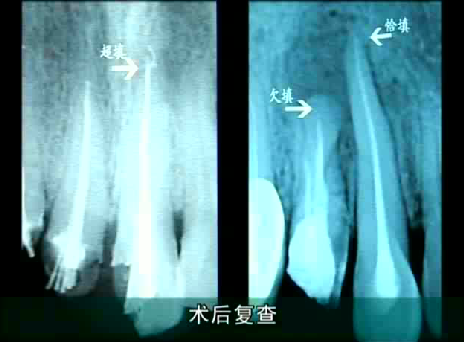

根管治療做完後拍片可見,超填、恰填和欠填的區別